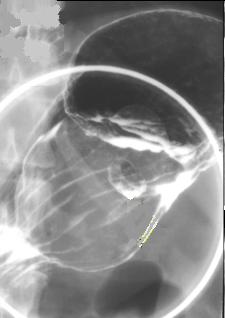

Image de nodule

pediculee a la petit courbure bord net et

lisse |

Image leiomyomes en proliferation

marquee intraluminale avec ulcere de surface

situe a la region antral de l' estomac( TOGD baryte

avec balloon compressif ventrale) |